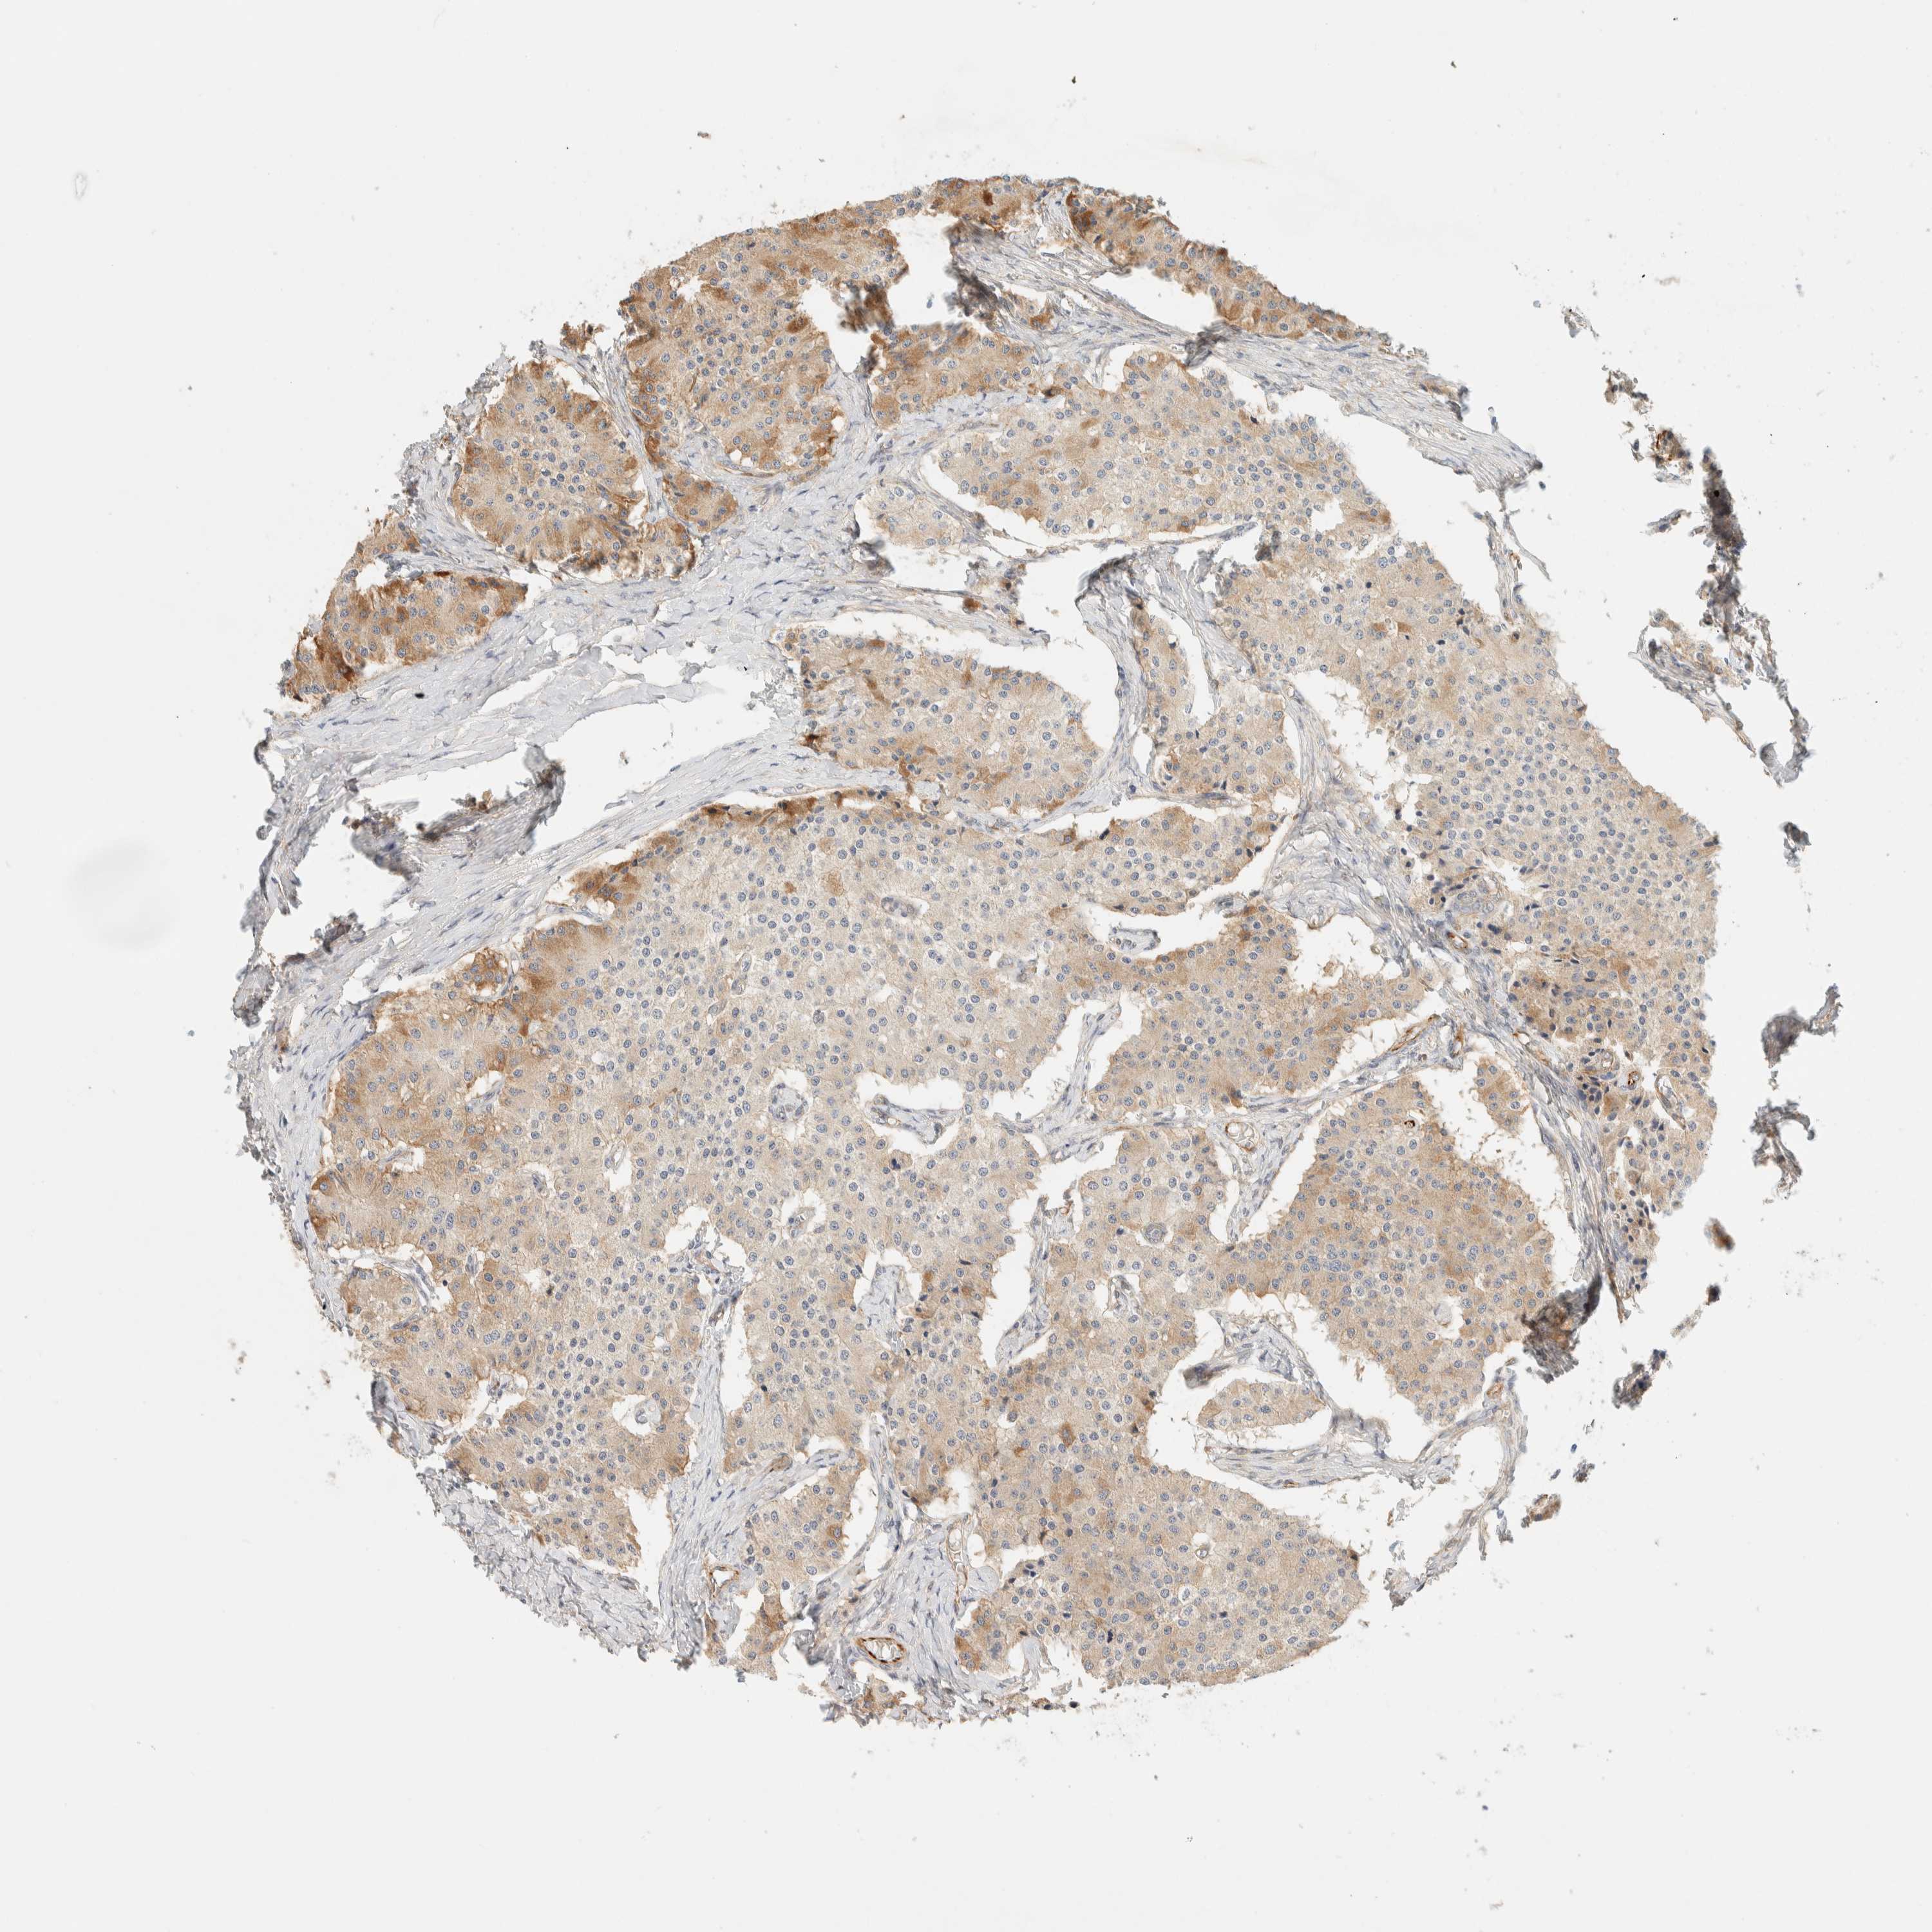

CARCINOID - Protein expressioni

A mouse-over function shows sample information and annotation data. Click on an image to view it in a full screen mode. Samples can be filtered based on level of antibody staining by selecting one or several of the following categories: high, medium, low and not detected. The assay and annotation is described here.

Antibody stainingi

Antibody staining in the annotated cell types in the current human tissue is reported as not detected, low, medium, or high, based on conventional immunohistochemistry profiling in selected tissues. This score is based on the combination of the staining intensity and fraction of stained cells.

Each image is clickable and will lead to virtual microscopy that enables deeper exploration of all samples and also displays staining intensity scores, fraction scores and subcellular localization as well as patient and tissue information for each sample.

Antibody HPA001869

Staining

High

Medium

Low

Not detected

Intensity

Strong

Moderate

Weak

Negative

Quantity

>75%

75%-25%

<25%

None

Location

Nuclear

Cytoplasmic/membranous

Cytoplasmic/membranous,nuclear

Carcinoid, malignant, NOS

Carcinoma, NOS